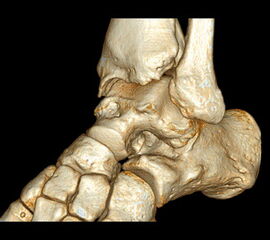

In den letzten Jahren hat die digitale Volumen Tomografie (DVT) erheblich an Bedeutung gewonnen. Der Vorteil dieses Verfahrens ist eine computertomografieartige Abbildung unter Vollbelastung des Fußes mit der Möglichkeit einer 3-D Rekonstruktion. Verglichen zur Computertomografie hat die DVT eine deutlich geringere Strahlenbelastung 12. Aus dem Datensatz lassen sich Projektionsbilder errechnen, sodass viele belastete konventionelle Aufnahmen durch eine DVT überflüssig werden.

Zur Vollansicht und zum Lesen der Bildbeschreibung bitte das Bild anklicken.